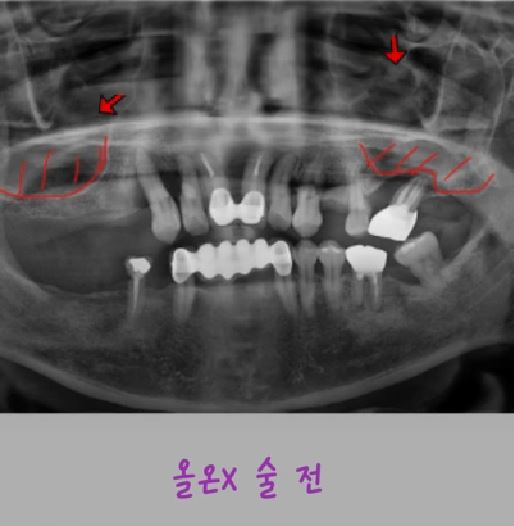

제목 뼈이식 최소한으로 빠르게 가능한 풀아치 임플란트, 올온X(All-on-X) 시술 안내

Emotion Icon올온X(All-on-X)란?

올온X는 소수의 임플란트를 전략적으로 식립하여

위 또는 아래 전체 치아를 한 번에 회복하는 풀아치 임플란트 치료법입니다.

기존 방식처럼 치아 하나하나를 심는 것이 아니라,

각도가 조절된 임플란트를 좋은 뼈에 선택적으로 식립하여

적은 개수의 임플란트로 전체 보철을 안정적으로 지지합니다.

Emotion Icon뼈이식을 최소한으로 할수있는  이유

치아를 오래 상실하면 잇몸뼈가 많이 흡수되어

기존 방식에서는 뼈이식이 필요한 경우가 많았습니다.

하지만 올온X는

✔ 뼈가 비교적 단단하게 남아있는 부위를 선택하여

✔ 임플란트를 각도 있게 식립함으로써

✔ 별도의 광범위한 뼈이식 없이도 치료가 가능한 경우가 많습니다.